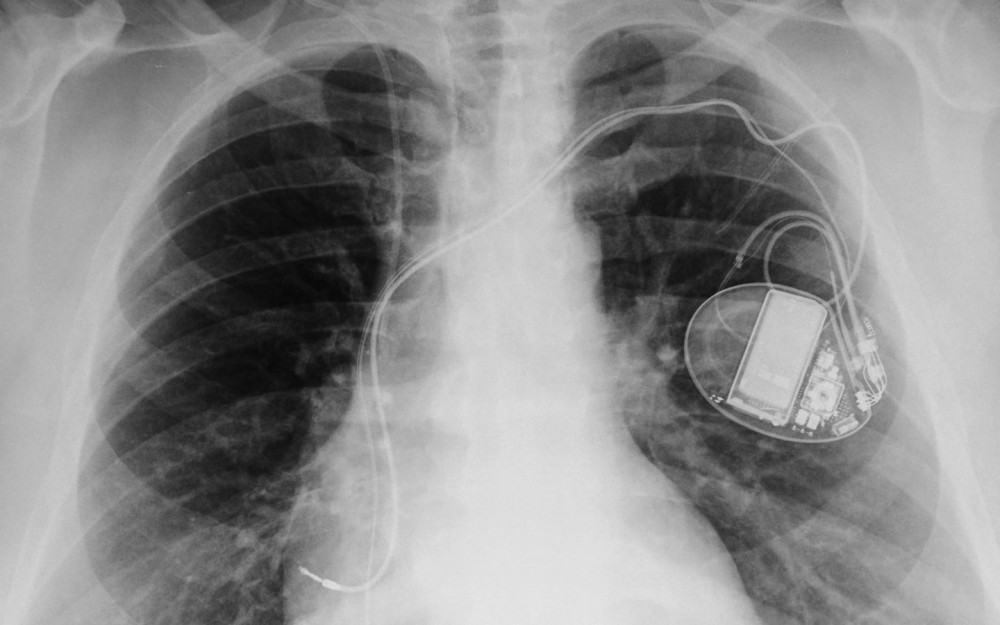

O esforço conjunto para explorar as “informações médicas interceptadas” ganhou notoriedade 13 anos mais tarde, à medida que dispositivos médicos e monitores corporais se integram cada vez mais à internet, ampliando as possibilidades de expandir o uso de informações coletadas além das epidemias e armas biológicas, para formas de vigilância mais específicas. O diretor assistente da NSA, Richard Ledgett, disse em junho que a agência de espionagem estava “estudando (…) teoricamente” a possibilidade de usar dispositivos médicos, como marca-passos, para vigiar pessoas, mesmo tendo admitido haver formas mais fáceis de espioná-las.